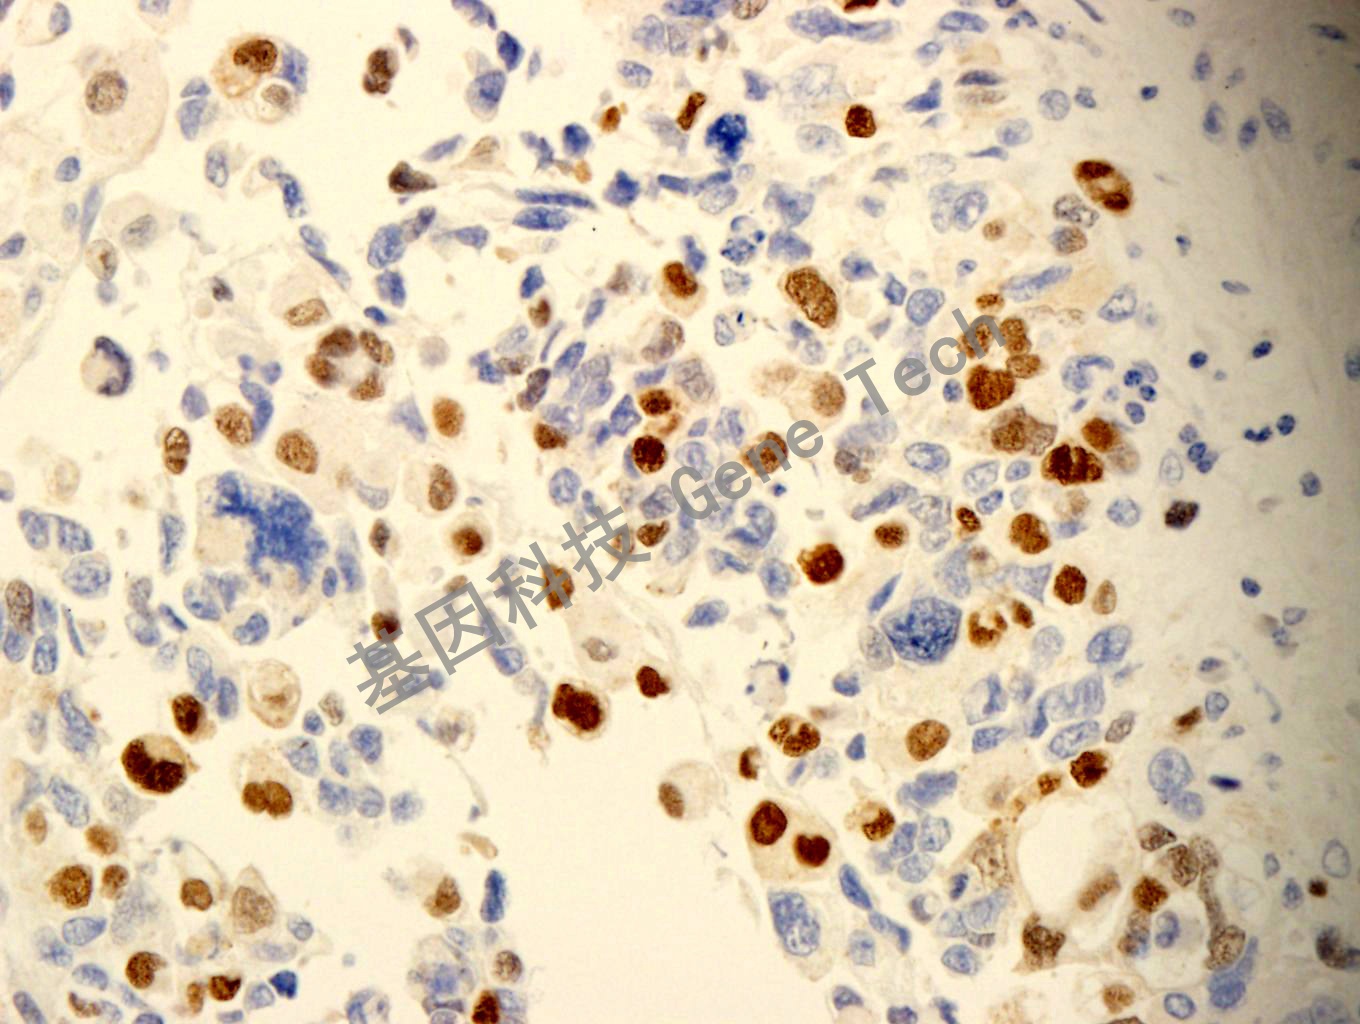

| 預(yù)處理:高pH熱修復(fù) | 陽性部位:細(xì)胞核 | 陽性對照:橫紋肌肉瘤 |

| 簡介:Myf-4與Myogenin同源,定位于分化細(xì)胞的核內(nèi),是骨骼肌特異性轉(zhuǎn)錄因子,為橫紋肌肉瘤的特異性標(biāo)記物。可用于橫紋肌肉瘤與神經(jīng)母細(xì)胞瘤、肝母細(xì)胞瘤、非霍奇金淋巴瘤、平滑肌瘤的鑒別診斷。 | ||

| 橫紋肌肉瘤石蠟切片,用 Myf-4(GT2269)染色,細(xì)胞核陽性,DAB 顯色。 | ||